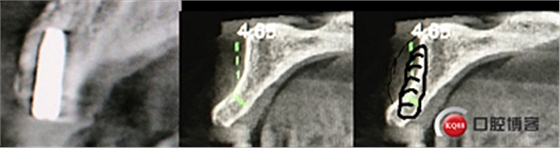

“以修復(fù)為導(dǎo)向”,在前牙種植體中心點(diǎn)就是未來(lái)牙冠舌側(cè)窩位置。那這個(gè)病例植體的方向和位置就只能是下圖右側(cè)這樣了。很明顯植體根尖部分要穿出唇側(cè)倒凹的。怎么辦?翻大瓣植骨蓋膜減張縫合?不!可以不翻瓣,大家仔細(xì)看看下圖右圖我畫(huà)的那條細(xì)細(xì)的弧線,是不是跟原來(lái)唇側(cè)凹陷的骨面成為左右對(duì)稱(chēng)的兩條弧,也就是說(shuō)骨膜從原來(lái)唇側(cè)凹陷骨面上剝離然后放到左側(cè)我畫(huà)的那條弧線那里根本不需要減張,這兩條弧線之間也就是唇側(cè)凹陷處放上骨粉,骨膜不會(huì)增加張力。不知道大家看明白了沒(méi)有。

設(shè)計(jì):1.僅做牙槽嵴頂水平切口,不做垂直切口,2.缺牙區(qū)由三顆牙改成兩顆牙,3.鄰牙冠延長(zhǎng)。